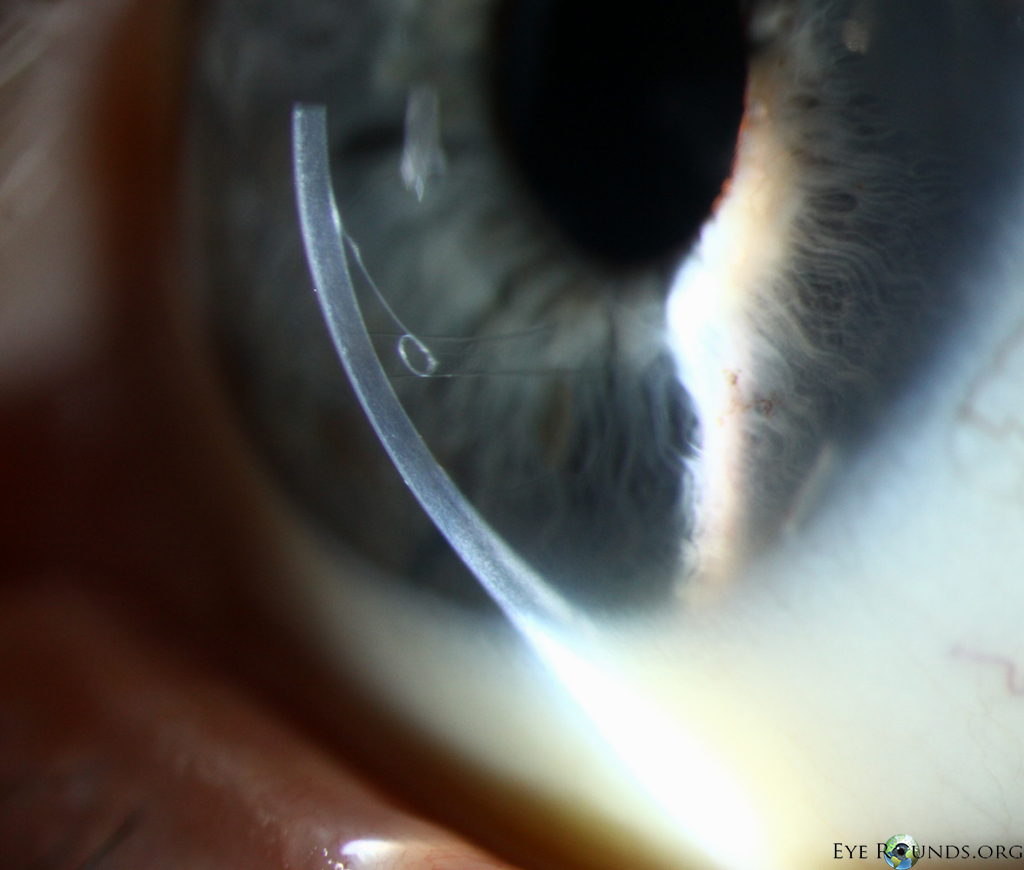

DMEK is a partial-thickness cornea transplant procedure that involves selective removal of the patient's Descemet membrane and endothelium, followed by transplantation of donor corneal endothelium and Descemet membrane without additional stromal tissue from the donor. The graft tissue is merely 10-15 microns thick. Similar to DSAEK, direct contact with the DMEK graft tissue should be avoided to prevent endothelial cell damage and graft failure. A clear corneal incision is created, the recipient endothelium and Descemet membrane are removed, and the graft is loaded into an inserter. After injecting the tissue into the anterior chamber, the surgeon orients and unscrolls the graft, and a bubble of 20% sulfur hexafluoride (SF6) is placed in the anterior chamber to support graft adherence (Figure 10). A variation known as Descemet membrane automated endothelial keratoplasty (DMAEK) utilized an automated preparation of the donor tissue that left a rim of donor stroma peripherally for easier tissue handling (Figure 11), but the procedure is no longer performed due to advances in DMEK that have allowed for easier insertion and manipulation of the graft tissue.

Because of thinness, fragility, and its characteristic scrolling properties (with the endothelium facing outward), the donor tissue can be difficult to handle and contribute to technical difficulties with the procedure. There is a higher risk of graft edge lifts (Figure 13) compared with DSAEK, sometimes requiring a re-bubble procedure.